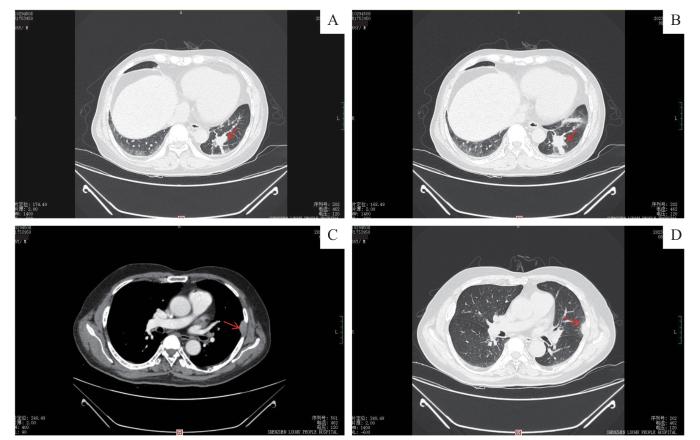

图2

胸部增强CT显像

Note: A/B. Two different layers of contrast-enhanced chest CT scans. Multiple elongated strip shadows are visible around the same site, and mild sustained enhancement is visible on contrast-enhanced scans (arrow). C. Contrast-enhanced chest CT showing a chest wall mass (arrow) at the mediastinal window level. D. Contrast-enhanced chest CT showing a chest wall mass (arrow) at the lung window level.

Fig 2

Contrast-enhanced chest CT scans

患者2017年诊断为MM,当时未合并髓外侵犯,经多次化疗病情缓解。2023年4月发现髓外病灶(肺及胸壁),伴咳嗽、咳痰等,考虑感染可能性大;予经验性抗真菌感染治疗后,患者肺部病灶稍有缩小,但效果不显著。2023年5月,PET-CT发现多灶性占位,左肺下叶后基底段结节状高代谢病灶,考虑左肺下叶周围型肺癌并阻塞性肺不张,左侧胸膜后(左侧第8后肋层面)结节状轻度高代谢病灶,考虑转移灶。不排除周围型肺癌或骨髓瘤侵犯,双侧胸膜上多发小片状及丘状增厚,代谢轻度增高,考虑双侧胸膜多发转移灶。此外,胸部CT增强不排除肺恶性肿瘤或骨髓瘤肺部侵犯,胸壁肿物不排除骨髓瘤转移可能(图2)。